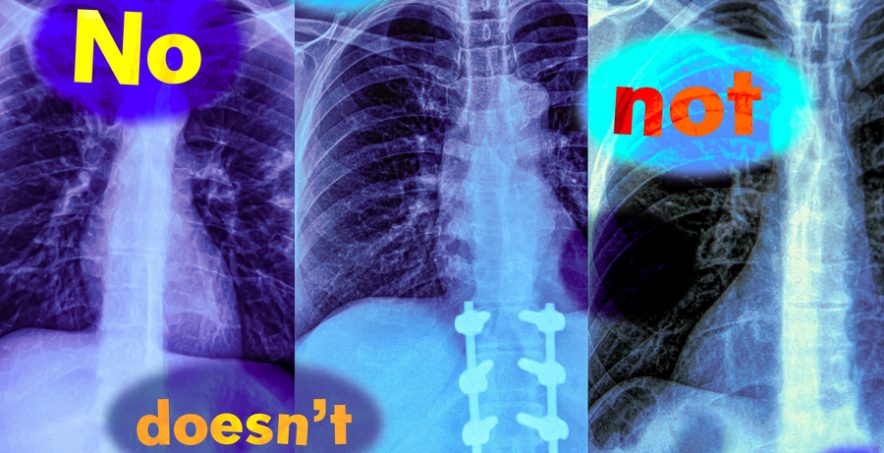

In a new study, MIT researchers have found that vision-language models are extremely likely to make such a mistake in real-world situations because they don’t understand negation — words like “no” and “doesn’t” that specify what is false or absent.